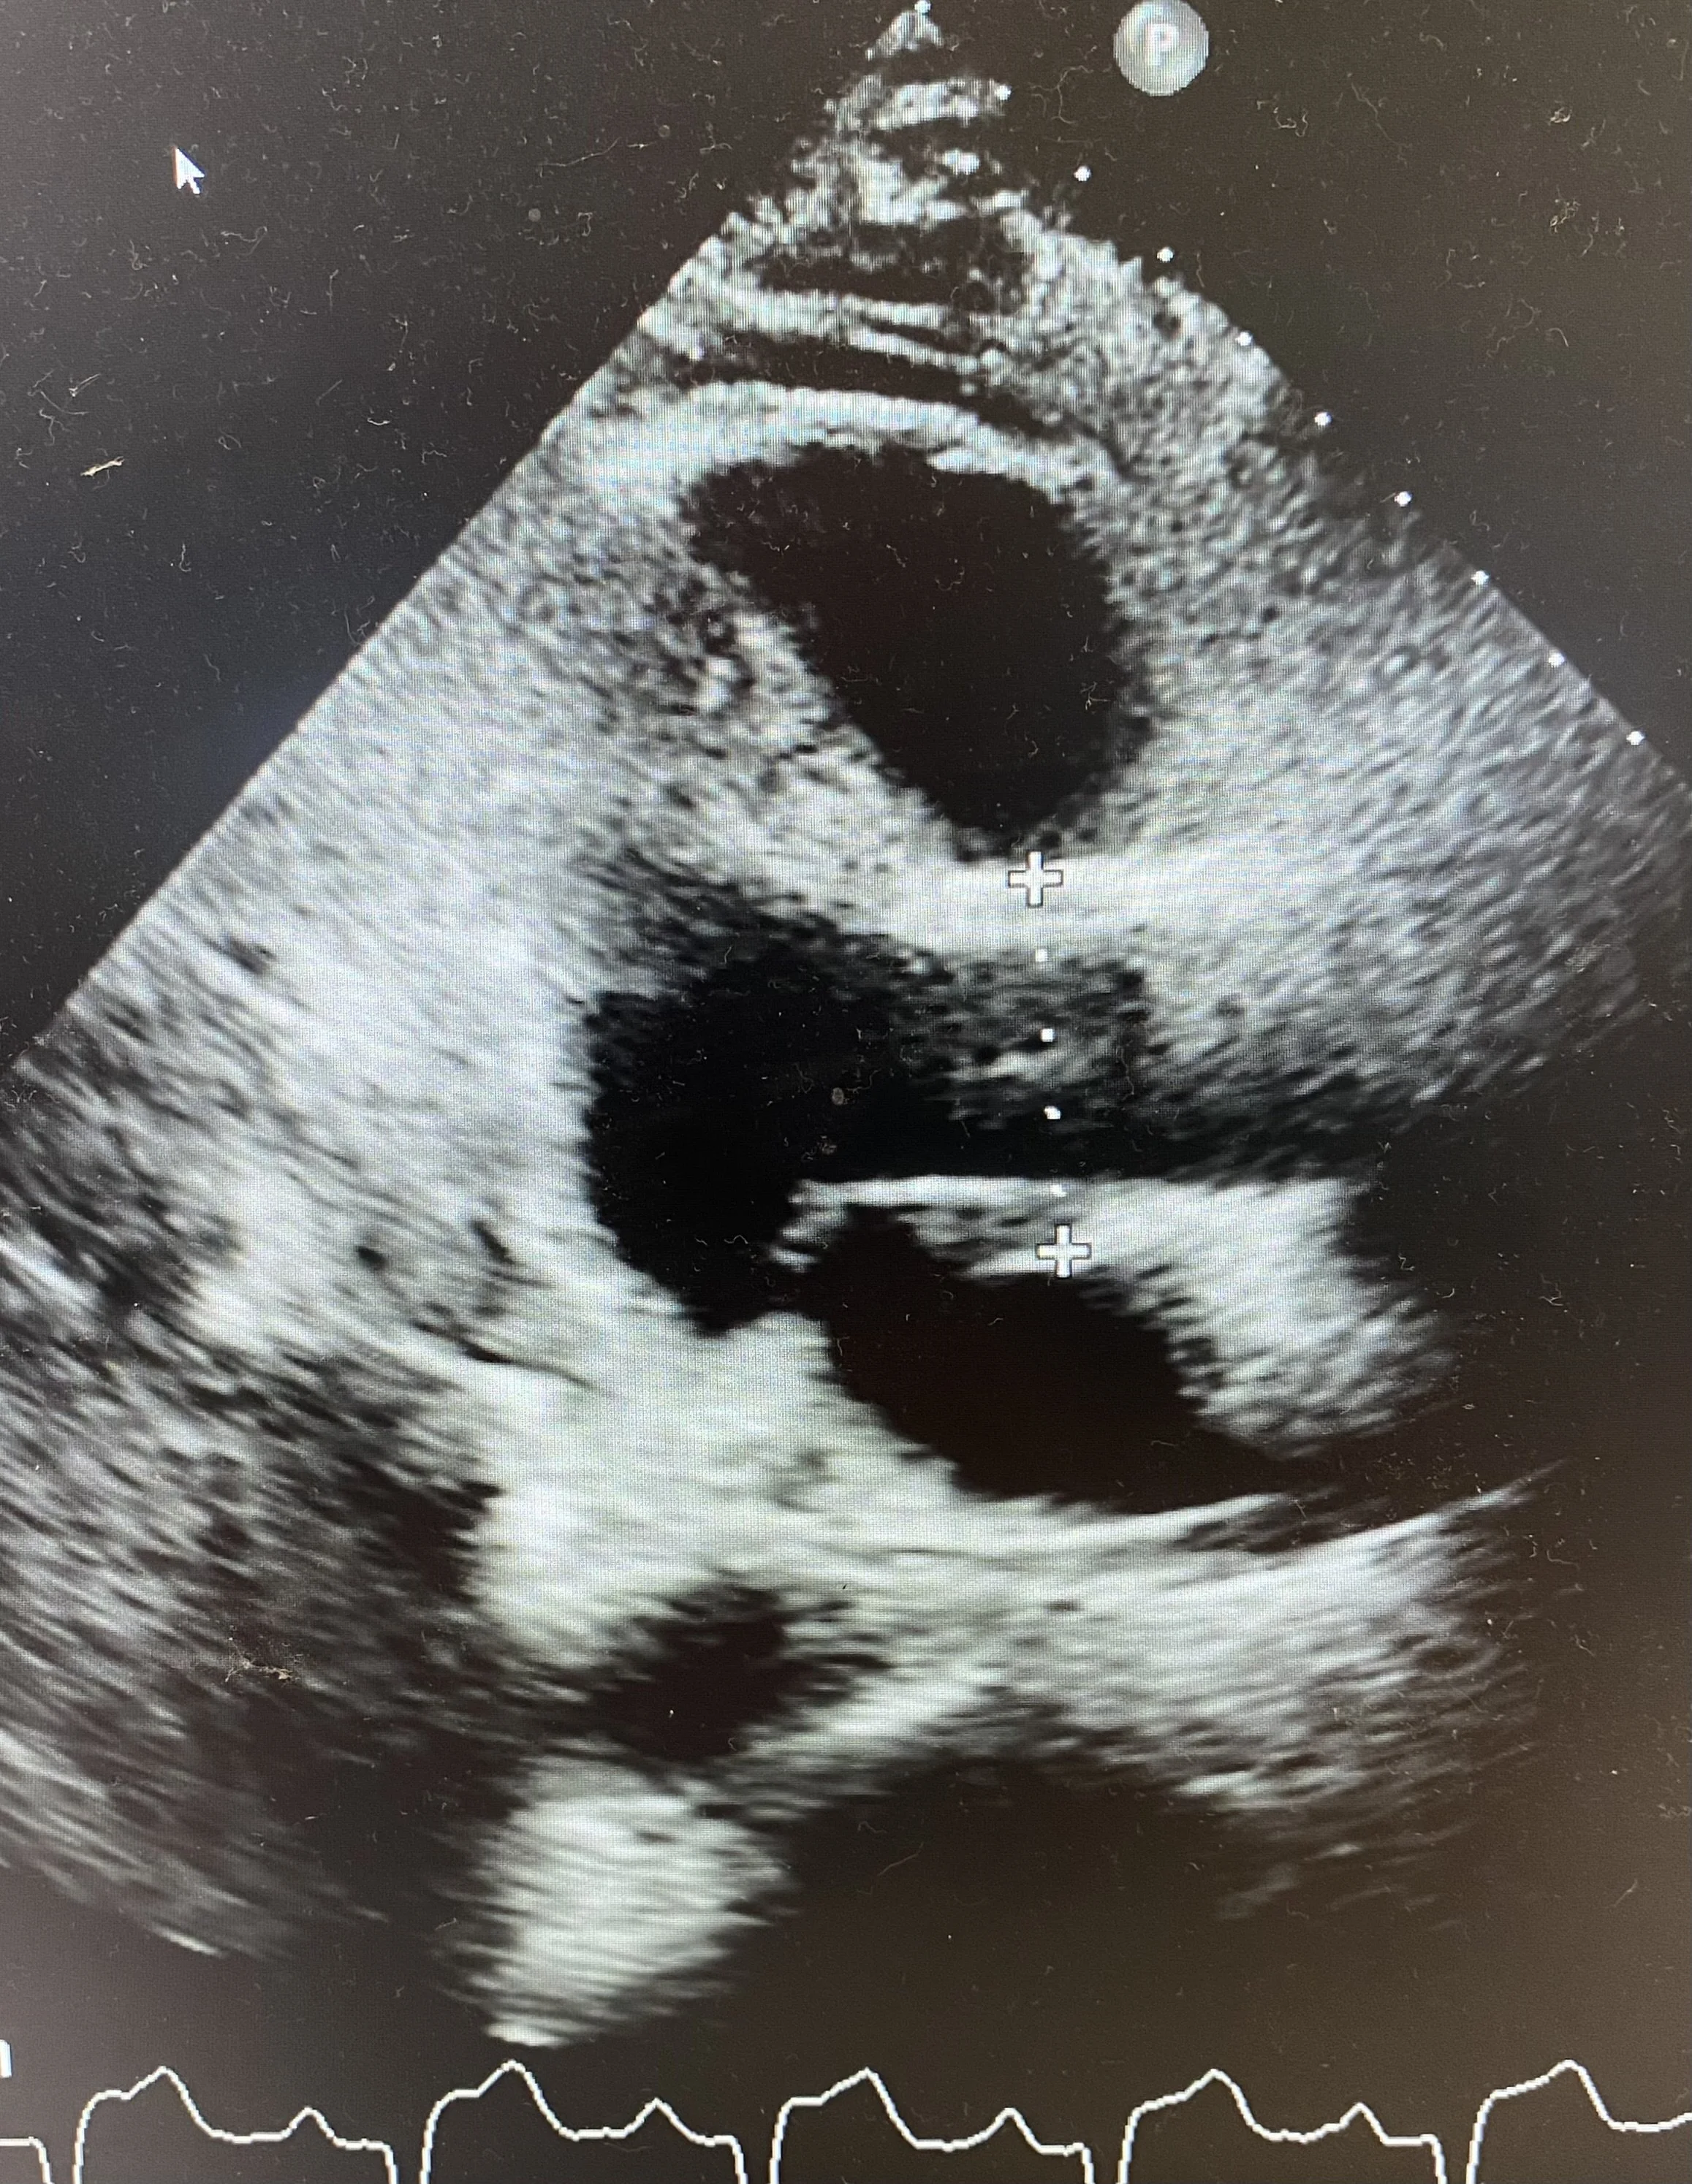

POCUS (shown below) showed a normal size aortic root and ascending aorta. There was no pericardial effusion.

See stills showing measurement of the Aortic Root (top) and the Ascending Aorta (bottom). From the Parasternal long-axis you may need to rotate the probe to open up the aortic root and measure the maximum width. Ensure the ascending aorta is measured above the sinutubular junction. Sometimes moving the probe up a whole rib-space allows the ascending aorta to be better visualised.

The measurements here were 3.8cm and 3.5cm respectively for aortic root and ascending aorta (normal).